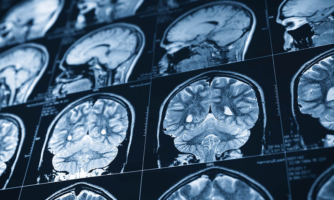

African Americans can significantly cut stroke risk by quitting smoking

African Americans are already almost twice as likely as whites to die from stroke. Now, new research finds that African Americans who smoke have more than double the risk ofRead More